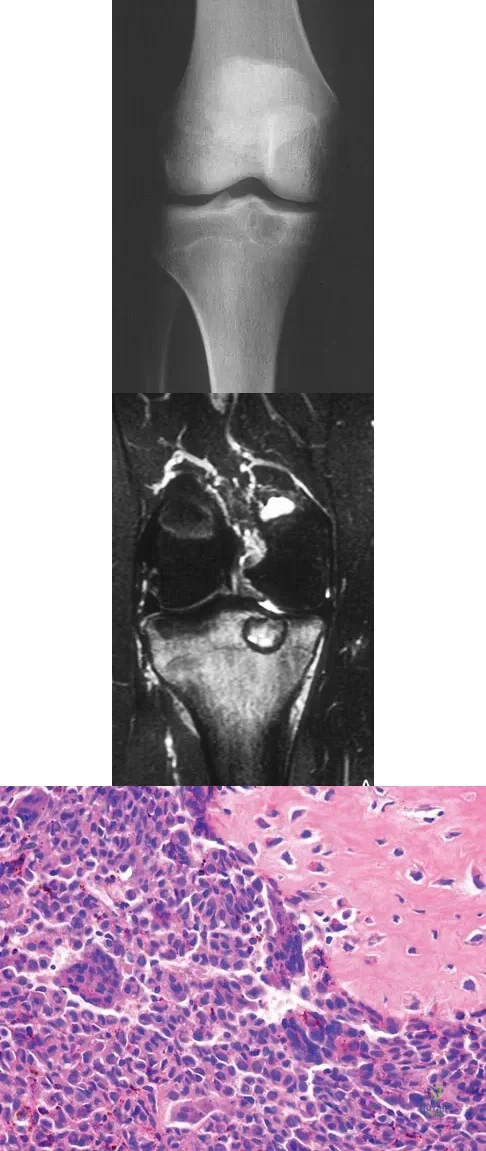

Question 35High Yield

A 15-year-old girl reports a 6-month history of activity-related knee pain and swelling. A radiograph, MRI scan, and biopsy specimen are shown in Figures 21a through 21c. What is the most likely diagnosis?

Explanation